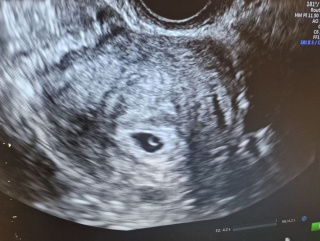

Во время ультразвукового обследования была выявлена субсерозная миома матки размером около 5 см, тип FIGO VII.

Беременность протекала хорошо, без осложнений.